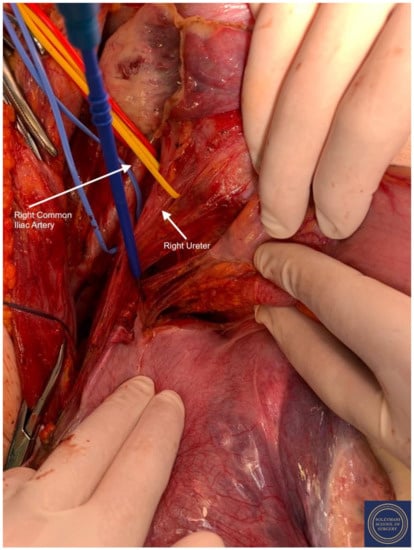

- Exposure of the infundibulo-pelvic ligaments and ureters were achieved with mobilization of the cecum, duodenum, and descending and sigmoid colon to the level of the common iliac vessel bifurcation with identification of the superior hypogastric plexus. The ureters, common iliac and internal and external iliac vasculatures were slung.

- -